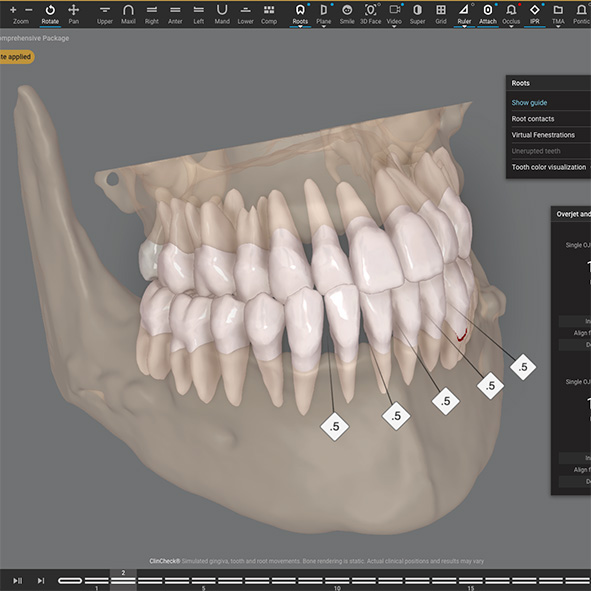

We’ll take a 3D scan of your teeth using our iTero scanner. This allows us to give you a detailed view of your current alignment and provide a visual explanation of the proposed treatment. This advanced technology makes it easier for you to see what to expect from your orthodontic journey.

3D simulation , Video Simulation

We will share your 3D simulation called ClinCheck with you. We now have the technology to simulate your smile not only from your picture but also to create a video simulation, so you can get a detailed, Dynamic Smile Simulation from the treatment made.